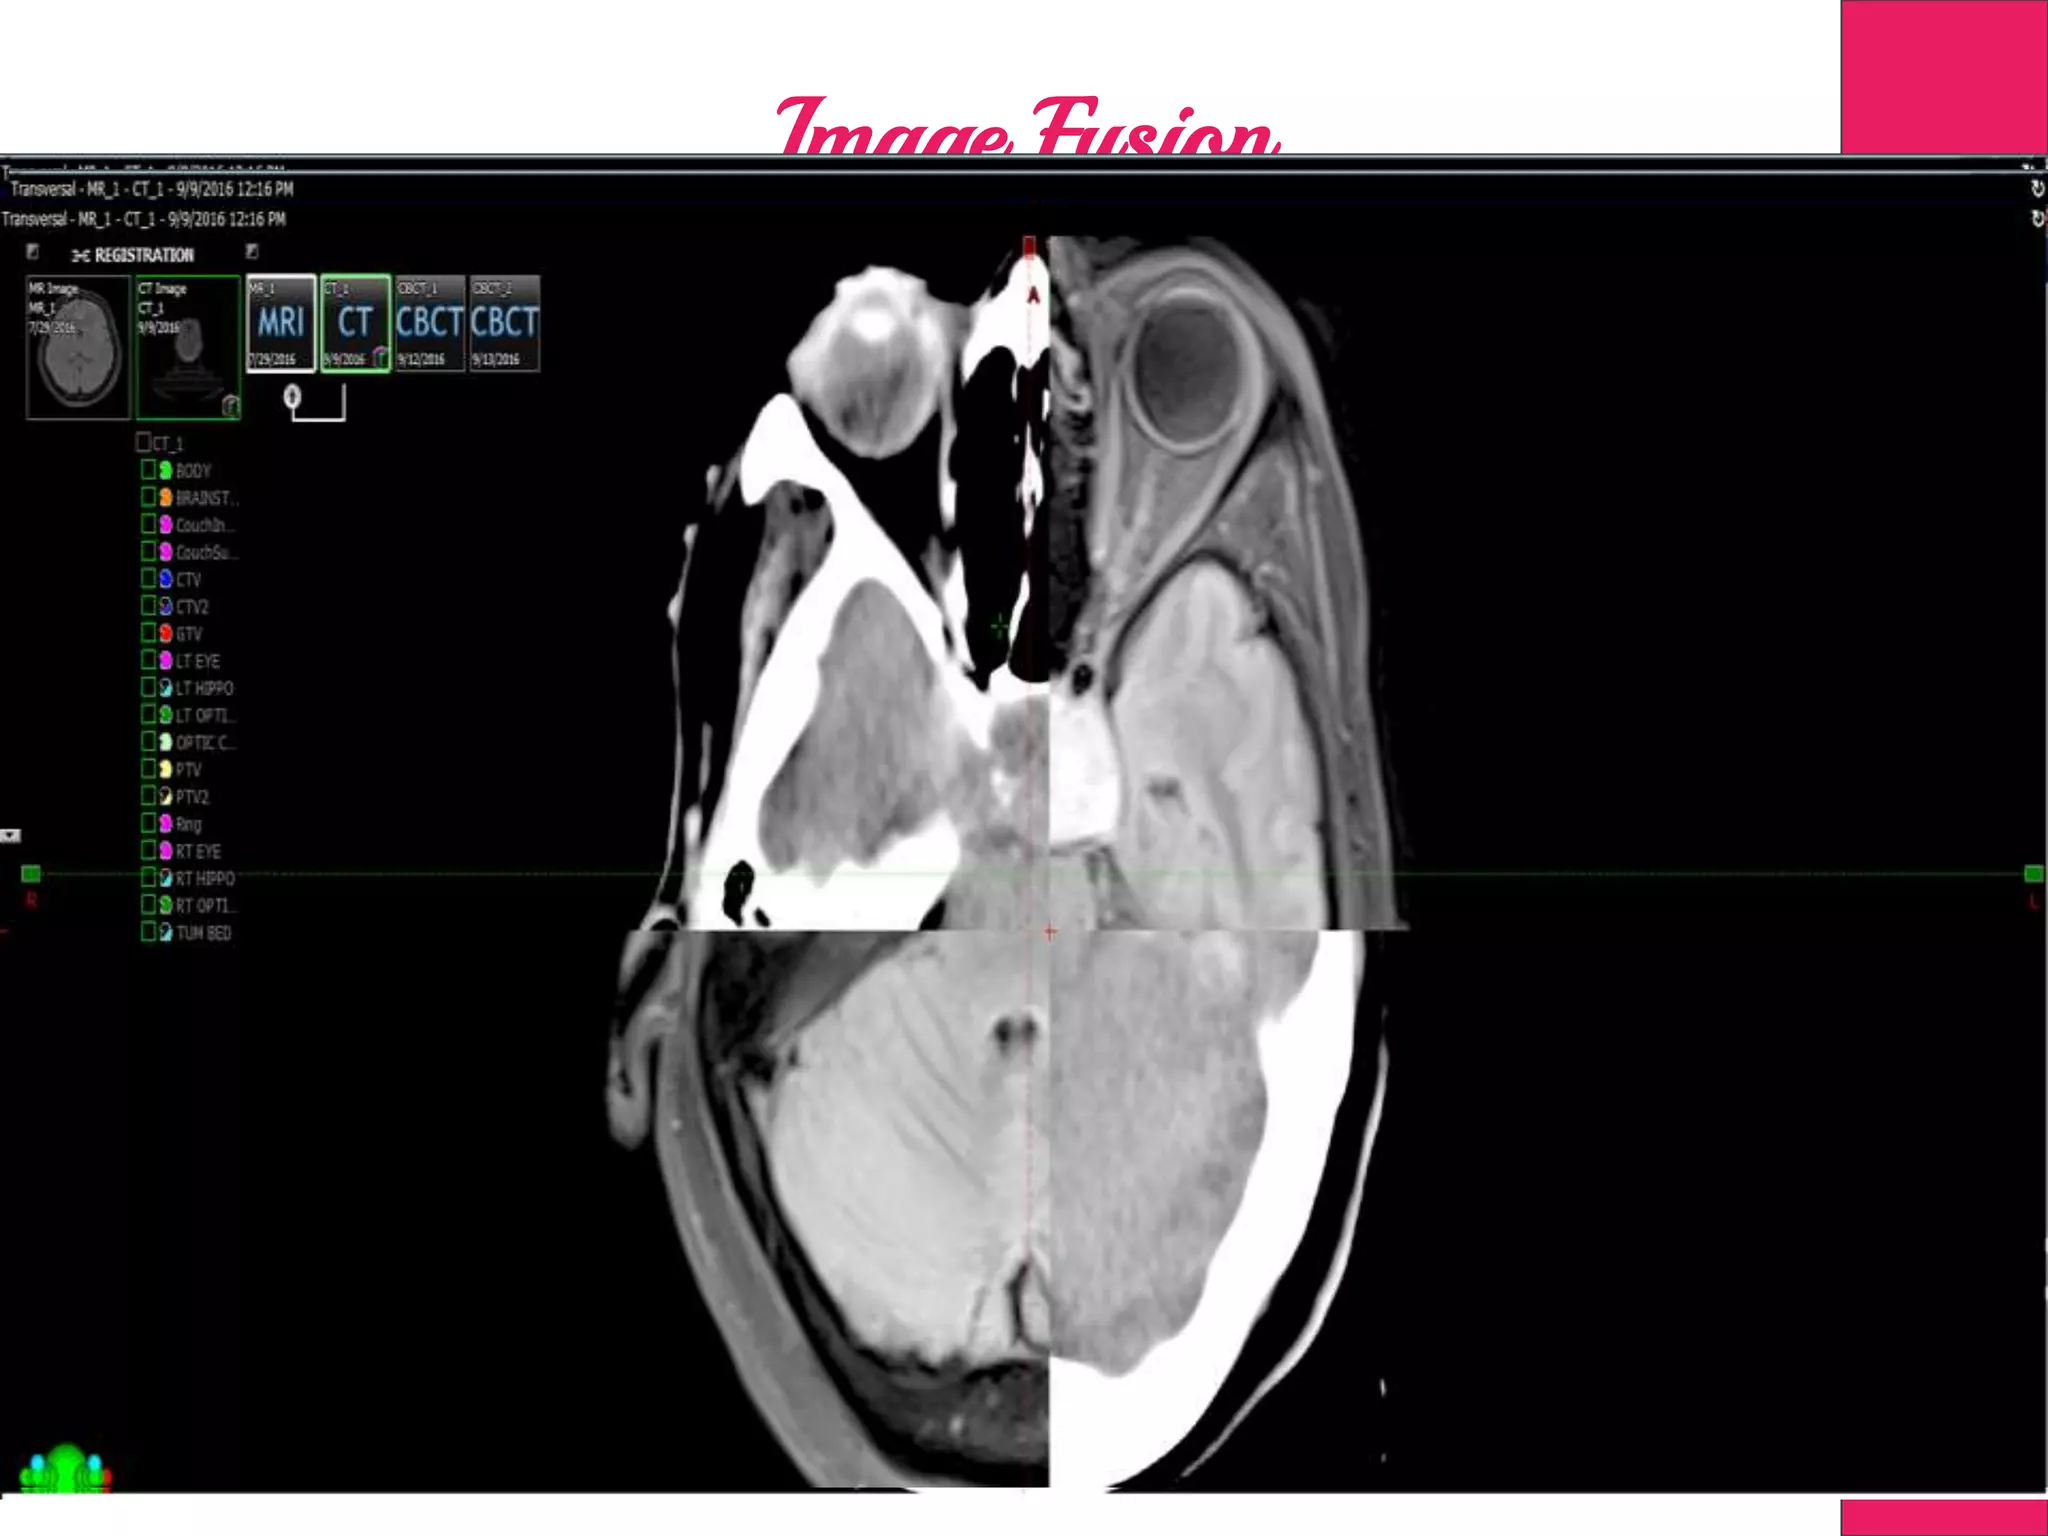

Image Fusion

Target Delineation

MR, PET, DSA &

4DCT